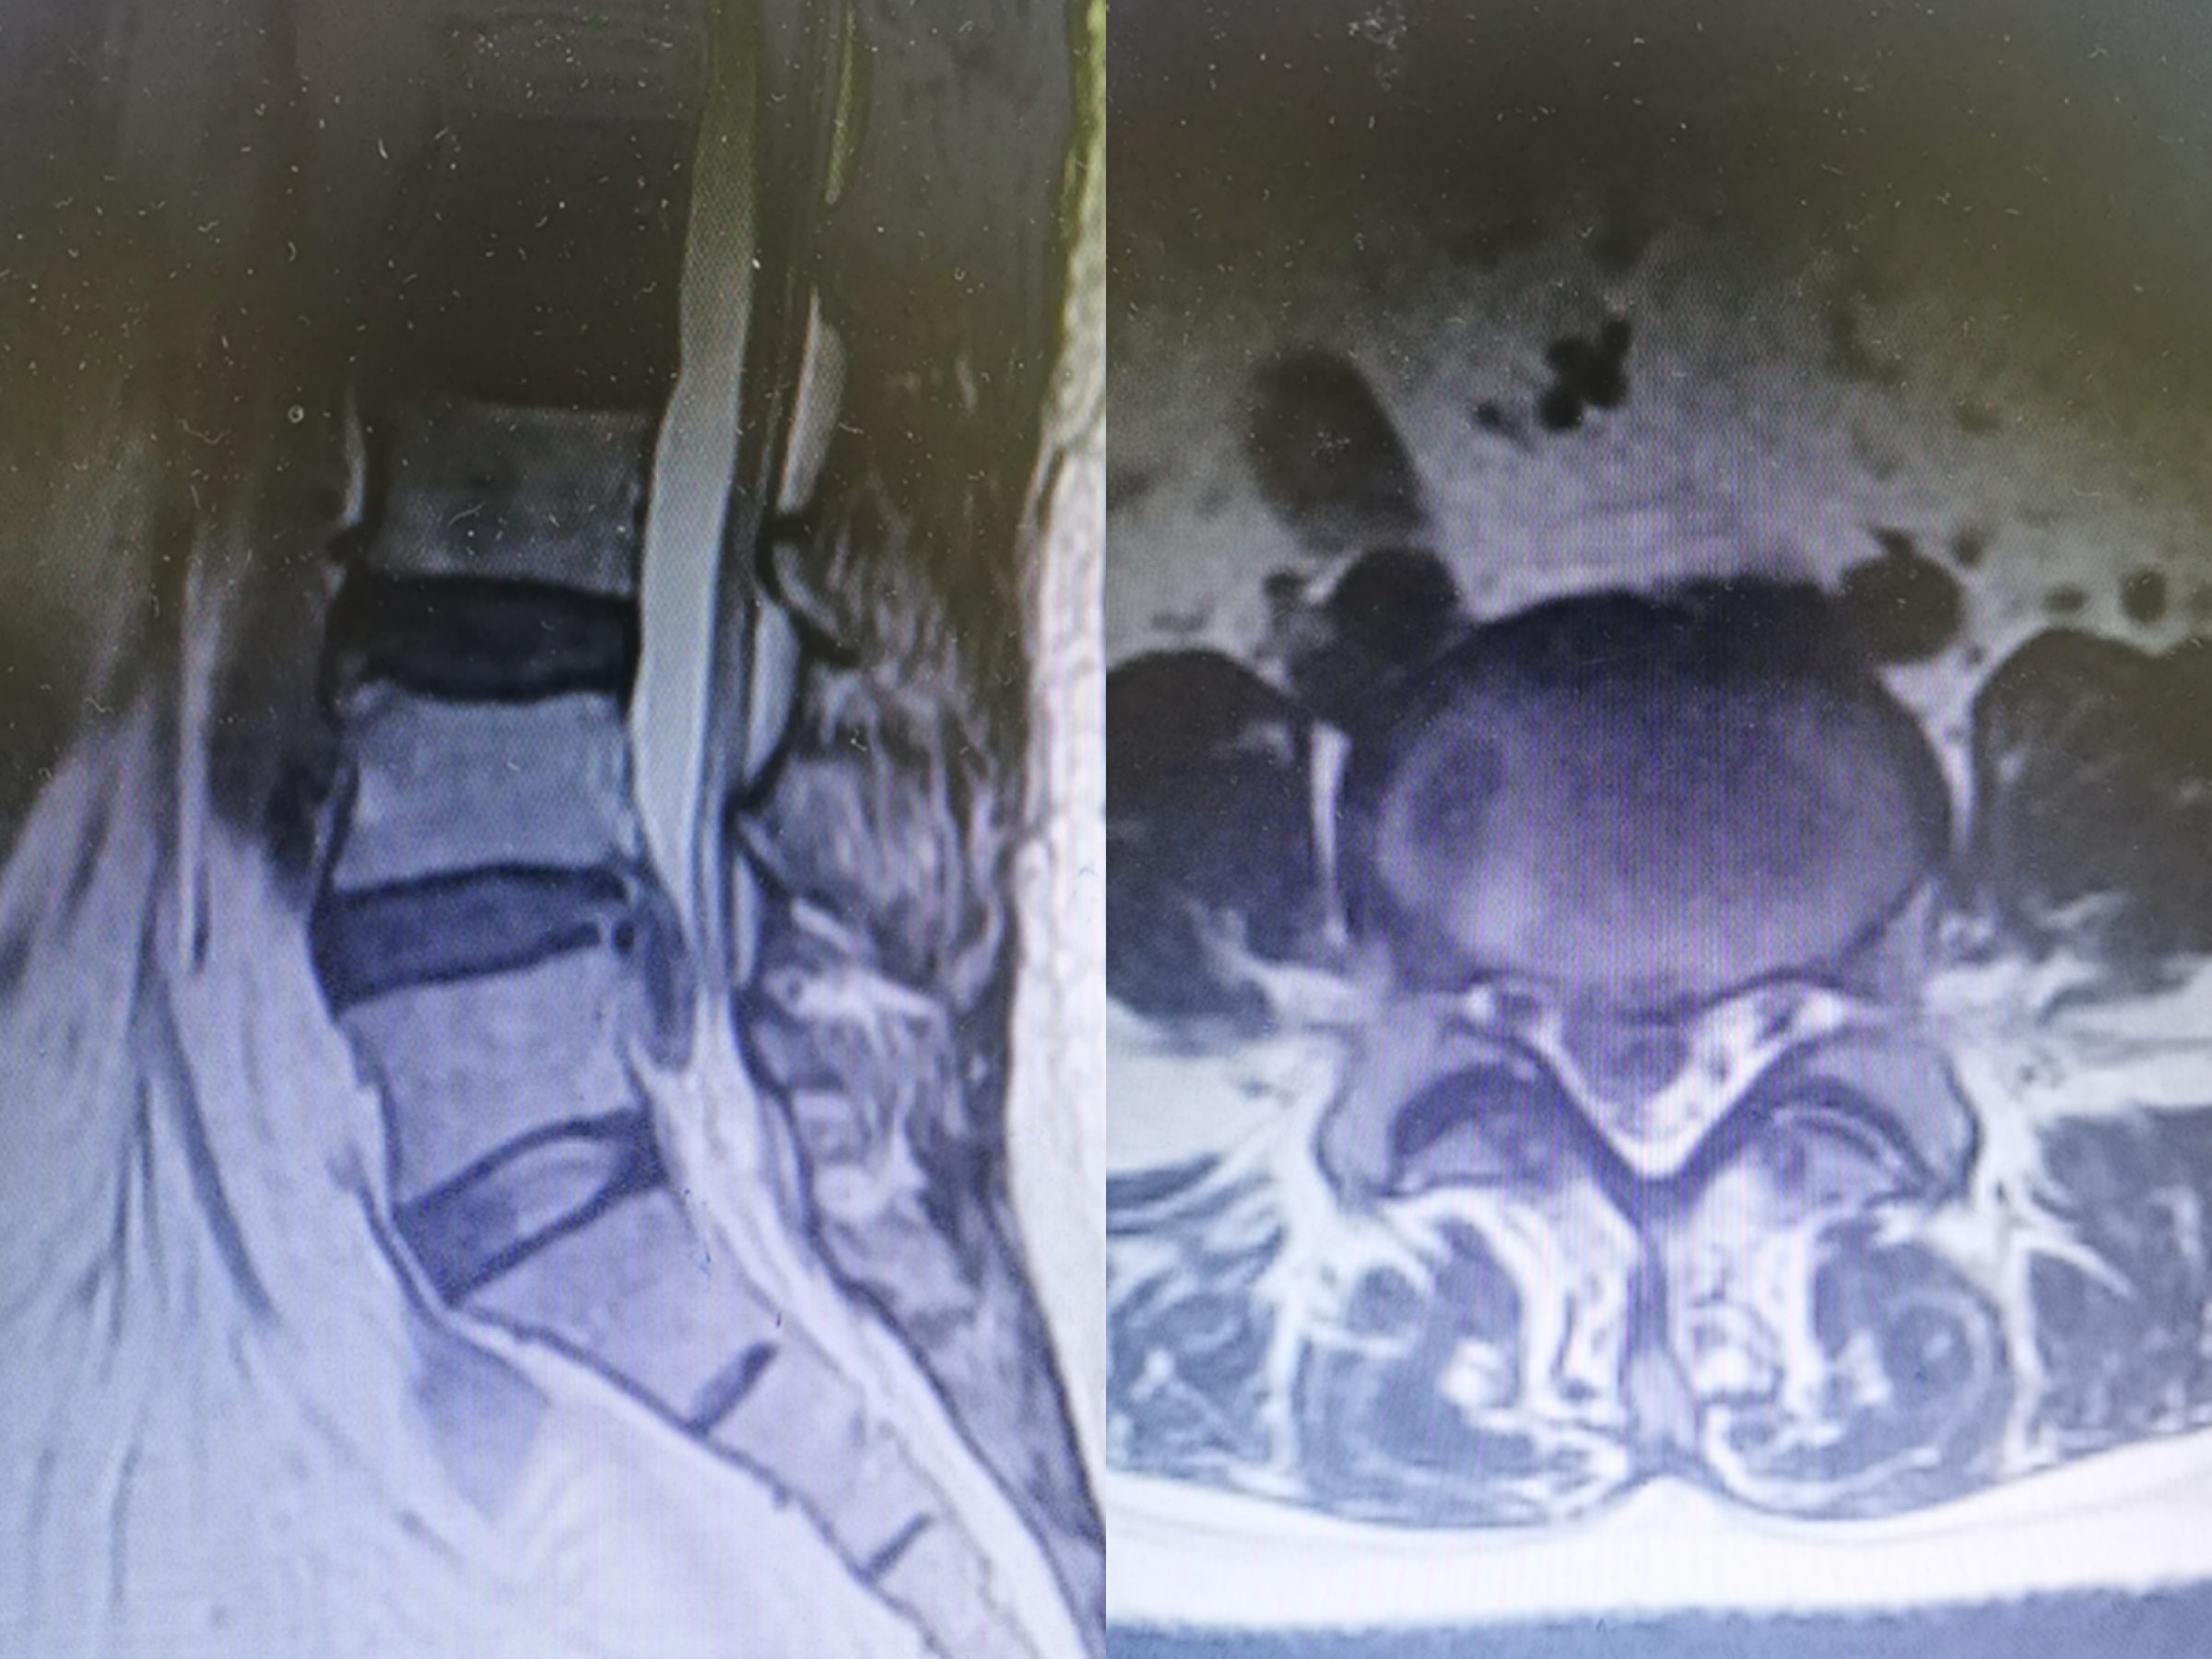

核磁共振显示腰椎间盘脱出

“医生,我这腰痛有10年了,总是反反复复的,而且这十来天右腿麻得好不舒服。”家住长沙56岁的刘女士在家人的陪伴下来到捷克论坛 疼痛科门诊就诊。接诊的曹启旺副主任医师详细询问病史并仔细的为其做体查,完善MRI后显示:L4/5椎间盘脱出,L4/5椎间盘及L5椎体水平椎管狭窄。经与患者及家属沟通同意后,曹主任及治疗团队为患者施行了脊柱内镜下L4/5椎间盘脱出摘除术,术后刘女士惊喜地表示:真的不麻了,效果满意。